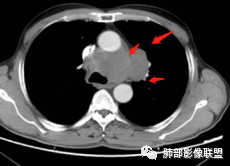

1.左肺门及纵隔见异常增大淋巴结,部分融合,不均匀轻度强化,未见明显坏死。

肿大淋巴结与纵隔血管等结构“无缝”贴合。

2.纵隔增宽但依旧居中。

1.这应当是常见的小细胞肺癌的转移方式。

别忘了,患者左肺上叶那个略显饱满的的小结节,有理由相信那是发源地。

因为这些符合肺癌的整个转移路径!

2、小细胞癌恶性程度高,发展迅速,转移发生早;常有纵隔淋巴结的明显增大融合(发生率达96.5%),呈“冰冻纵隔”,淋巴转移常为逐站的连续性转移;亦有血行转移,脑、肾上腺、肝、胰、骨髓等;转移灶常比原发灶大得多,即“娘小崽大”特点;